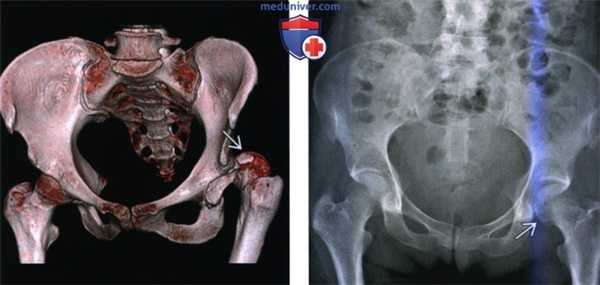

(Слева) КТ в передне-задней проекции, объемная 3D реконструкция: определяется задний вывих головки бедренной кости. КТ выполняется перед закрытой репозицией только если она оказалась неудачной. КТ позволяет оценить положение смещенных осколков, препятствующих репозиции.

(Справа) Рентгенография в передне-задней проекции, выполненная спустя год после заднего вывиха бедра: определяется латеральный подвывих левой головки бедренной кости и нарушение конгруэнтности сустава. Посттравматическая нестабильность бедра является известным, но плохо изученным феноменом.